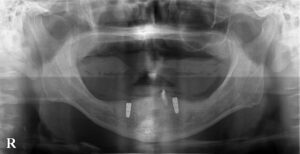

普段から通院していただいている優しい患者様に許可をいただいたので写真を掲載します。

もともと下の歯が1本だけ残った状態の上に総入れ歯(総義歯)を使用していただいていたのですが、安定感をより増やすために、数年前に残っている歯と義歯にアタッチメントとよばれる器具を設置しました。

そこでかねてからお話をしていたインプラントを2本埋入し、残っている歯の負担軽減と、義歯の安定を図る計画を立てました。

写真のインプラントに使用したアタッチメントはロケーターです。